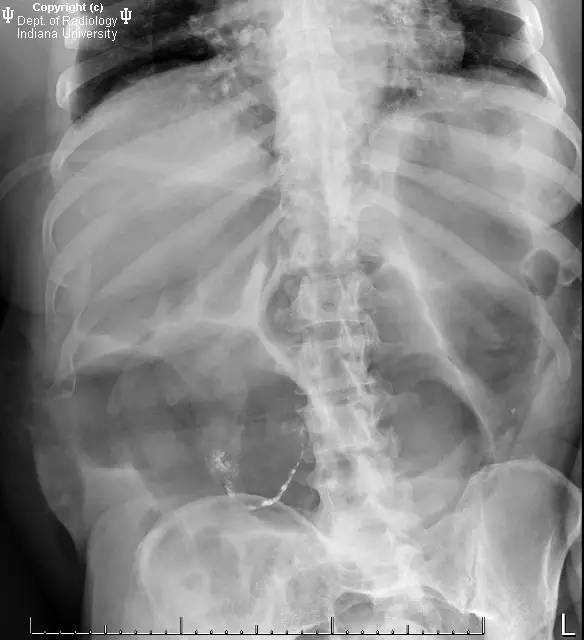

此为1周后复查图片。

【影像学表现】右侧腹部可见曲线样不透亮区,1周后位置有变化(似进入盲肠)。横结肠显著扩张、充气。CT上扩张原因不明,无明确的梗阻证据。

【诊断】阑尾内对比剂充填